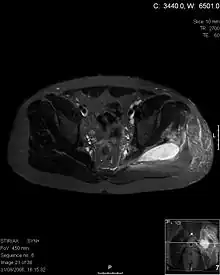

| Transverse T2 magnetic resonance imaging section through the hip region showing abscess collection in a patient with pyomyositis. | |

| Diagnostic method | Diagnostic method used for PM includes ultrasound, CT scan and MRI. Ultrasound can be helpful in showing muscular heterogeneity or a purulent collection but it is not useful during the first stage of the disease. CT scan can confirm the diagnosis before abscesses occur with enlargement of the involved muscles and hypodensity when abscess is present, terogenous attenuation and fluid collection with rim enhancement can be found. MRI is useful to assess PM and determine its localization and extension |